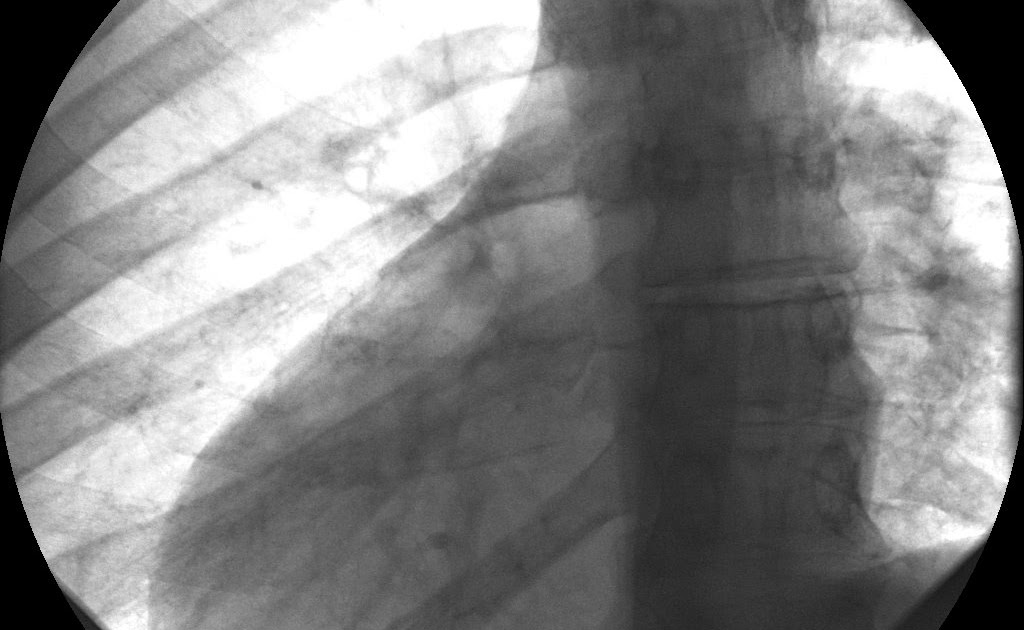

Diagnosis of situs inversus can be made using imaging techniques such as x-ray, ultrasound, CT scan, and magnetic resonance imaging (MRI).

The condition affects all major structures within the thorax and abdomen. Generally, the organs are simply transposed through the sagittal plane. The heart is located on the right side of the thorax, the stomach and spleen on the right side of the abdomen and the liver and gall bladder on the left side. The heart's normal right atrium occurs on the left, and the left atrium is on the right. The lung anatomy is reversed and the left lung has three lobes while the right lung has two lobes. The intestines and other internal structures are also reversed from the normal, and the blood vessels, nerves, and lymphatics are also transposed.

If the heart is swapped to the right side of the thorax, it is known as "situs inversus with dextrocardia" or "situs inversus totalis". If the heart remains on the normal left side of the thorax, a much rarer condition (1 in 2,000,000 of the general population), it is known as "situs inversus with levocardia" or "situs inversus incompletus".